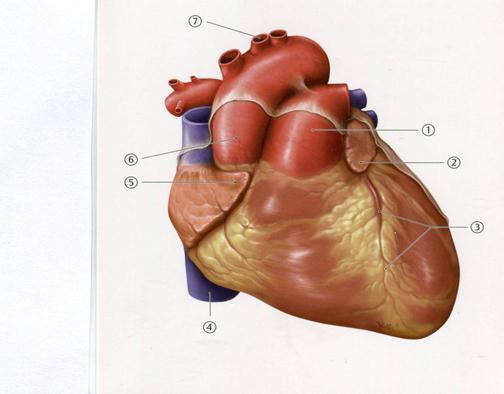

36. Төменде көрсетілген суреттегі белгіленген № 1 анатомиялық құрылымды атаңыз.

А. Қолқа

В. Оң жақ құлақша

+С. Өкпе сабауы

D. Сол жақ жалпы ұйқы артерия

Е. Төменгі қуыс вена

37. Төменде көрсетілген суреттегі белгіленген № 4 анатомиялық құрылымды атаңыз.

43. Төменде көрсетілген суреттегі белгіленген №7венаны атаңыз.

А. Артқы қабырғааралық

В. Бел

С. Жоғарғы қуыс

D. Жартылай сыңар

+Е. Сыңар